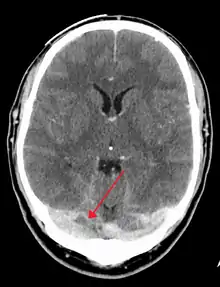

A dural venous sinus thrombosis of the transverse sinus. Greater on the right than left.

There are various neuroimaging investigations that may detect cerebral sinus thrombosis. Cerebral edema and venous infarction may be apparent on any modality, but for the detection of the thrombus itself, the most commonly used tests are computed tomography (CT) and magnetic resonance imaging (MRI), both using various types of radiocontrast to perform a venogram and visualise the veins around the brain.[3]

Magnetic resonance venography employs the same principles, but uses MRI as a scanning modality. MRI has the advantage of being better at detecting damage to the brain itself as a result of the increased pressure on the obstructed veins, but it is not readily available in many hospitals and the interpretation may be difficult.[11]